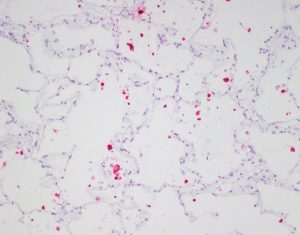

尽管有这些障碍,但一些病毒仍然可以感染大脑。当发生这种情况时,它们经常会导致致命疾病。Wiley教授审查了出苗的病毒感染和他们在过去的50年里造成的神经病理学。这里有一些例子。

Wiley教授审查了出苗的病毒感染和它们在过去50年中引起的神经病理学。

目前已知的冠状病毒有七种。其中四种是地方性的,这意味着它们在人类中广泛传播。对大多数人来说,它们只会导致感冒。另外三种已知的人类冠状病毒疑似来自蝙蝠,并通过中间宿主传播给人类:棕榈果子狸传播的是严重急性呼吸综合征冠状病毒(SARS-CoV),骆驼传播的是中东呼吸综合征冠状病毒(MERS-CoV),穿山甲可能传播的是SARS-CoV-2(也称为COVID-19)。所有这三种冠状病毒介导了严重肺炎,它们在人类中的出现是出乎意料的。虽然SARS-CoV和MERS-CoV的传播有限(分别在世界上造成约800人死亡),但COVID-19已经扰乱了我们的生活一年多。精神错乱、注意力不集中、味觉和嗅觉丧失,甚至失去意识、癫痫和中风等症状表明,COVID-19影响(尽管可能不会直接感染)人类大脑。